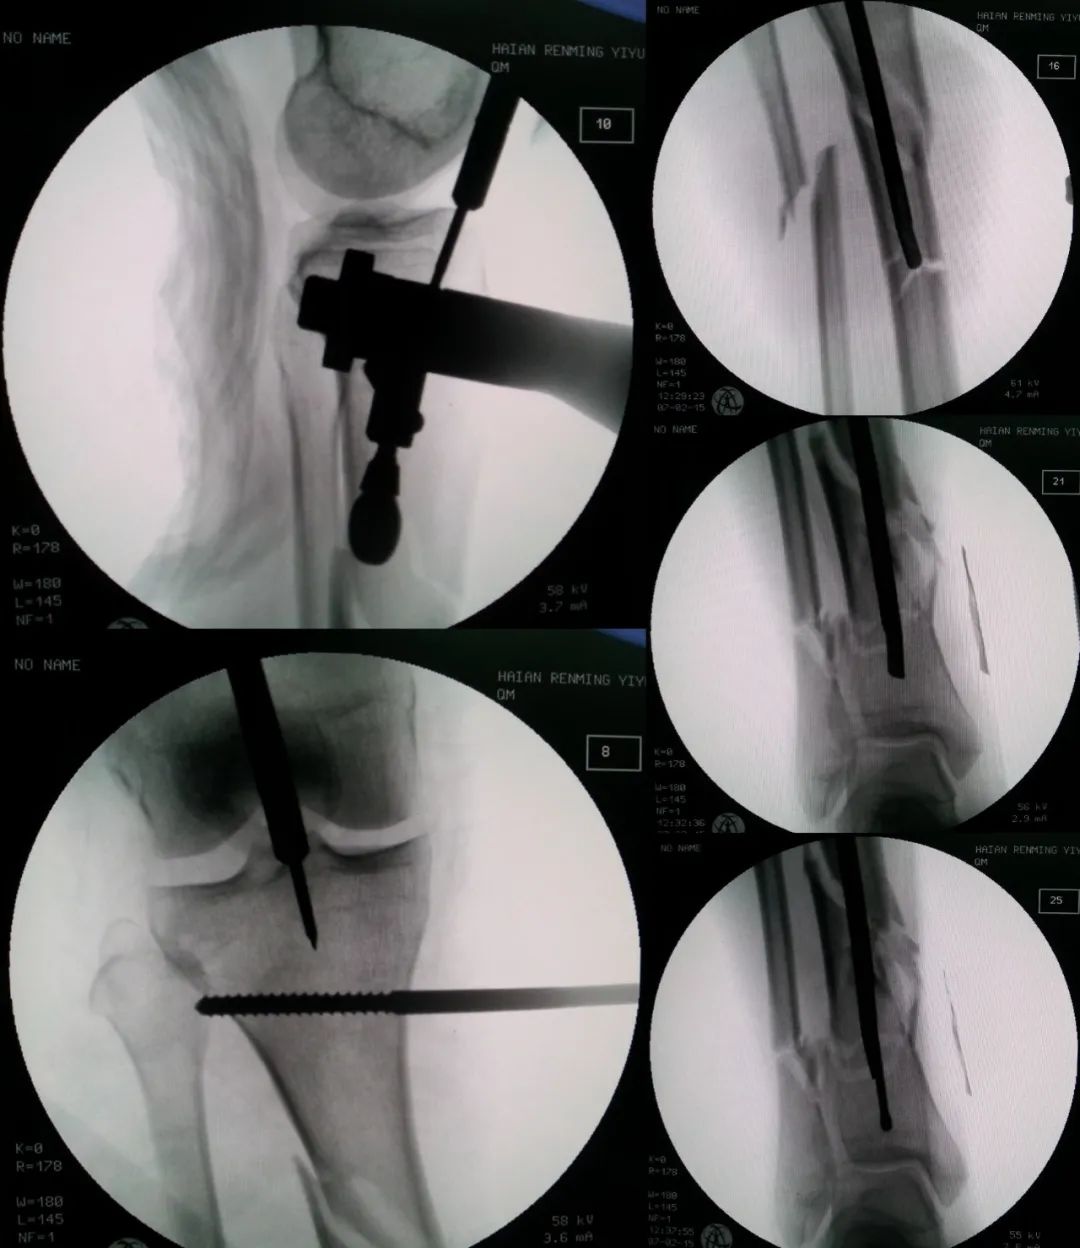

导读:不说废话,直接上图 !!!患者,女,50 岁,交通伤。诊断: 右胫腓骨开放性粉碎性骨折。胫骨后缘未见骨折,骨折线距踝关节平面不足 4 cm小腿下端前侧约 10 cm 创口,急诊清创...

诊断: 右胫腓骨开放性粉碎性骨折。

小腿下端前侧约 10 cm 创口,急诊清创,跟骨牵引,肿胀逐渐消退,白细胞、CRP、血沉等炎症指标降至正常范围。

最终选择髌骨上入路髓内钉固定。

1、使用牵开器维持骨折端基本的对位,对线。省时,省力不吃射线。

2、近端通过阻挡钉技术辅助骨折断端复位。

3、使用特殊的「 锁定型髓内钉 」远端即便只锁 2 枚锁钉依然稳定。